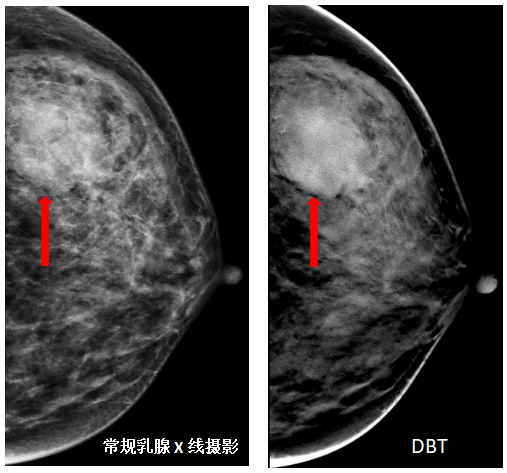

DBT

DBT(Digital Breast Tomosynthesis),意为“数字化乳腺断层摄影”,是一种三维成像技术。其原理是X线管球在有限的角度范围内旋转,进行一系列低剂量曝光,在较短时间内得到一系列断层图像。扫描完成后,计算机利用算法把图像重建为平行于探测器且间距为1mm左右的影像相对于传统的二维乳腺摄影技术,重建后的三维断层影像明显减少了组织重叠。致密性乳腺、微钙化、结构扭曲的患者就很适合采用这种检查方法,避免因腺体太过致密而掩盖了小病灶的显示。